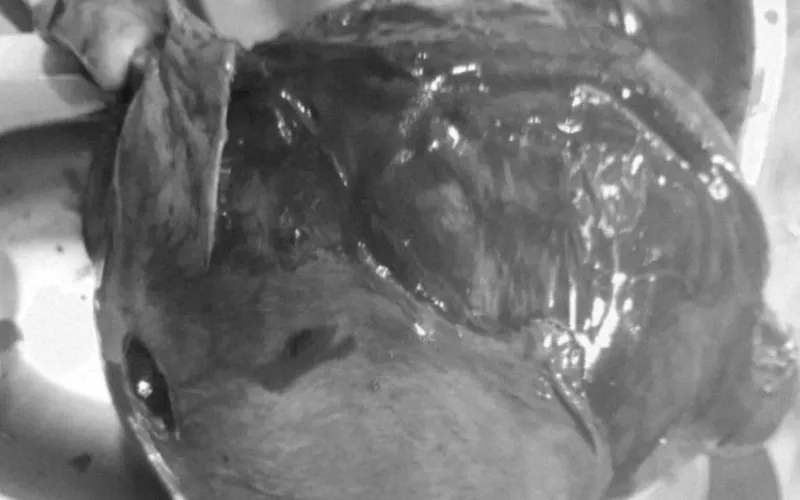

डोटीको साजघाटकी ४३ वर्षीया उत्तरा बोगटीको पाठेघरको जटील शल्यक्रिया गरिएको छ। पाठेघरमा आन्द्रा, अण्डाषय र पिसावथैली टासीएर समस्यामा परेकी उनको धनगढी स्थित निसर्ग अस्पतालमा शल्यक्रिया गरिएको हो।

सल्यक्रियापछि बिरामीको अबस्था सामान्य रहेको निसर्ग हस्पिटल एण्ड रिसर्च सेन्टर प्रालिका अध्यक्ष तीर्थ पन्तले बताए। निसर्ग अस्पतालका स्त्रीरोग विशेषज्ञ डाक्टर नजमुस्सबा अन्सारी, एनेस्थेसियोलोजिस्ट डा. हेमन्त ओझा, वरिष्ठ जनरल तथा ल्याप्रोस्कोपिक सर्जन डा. मिराज आलम अन्सारी लगायतको टिमले बोगटीको सफल सल्यक्रिया गरेको हो।